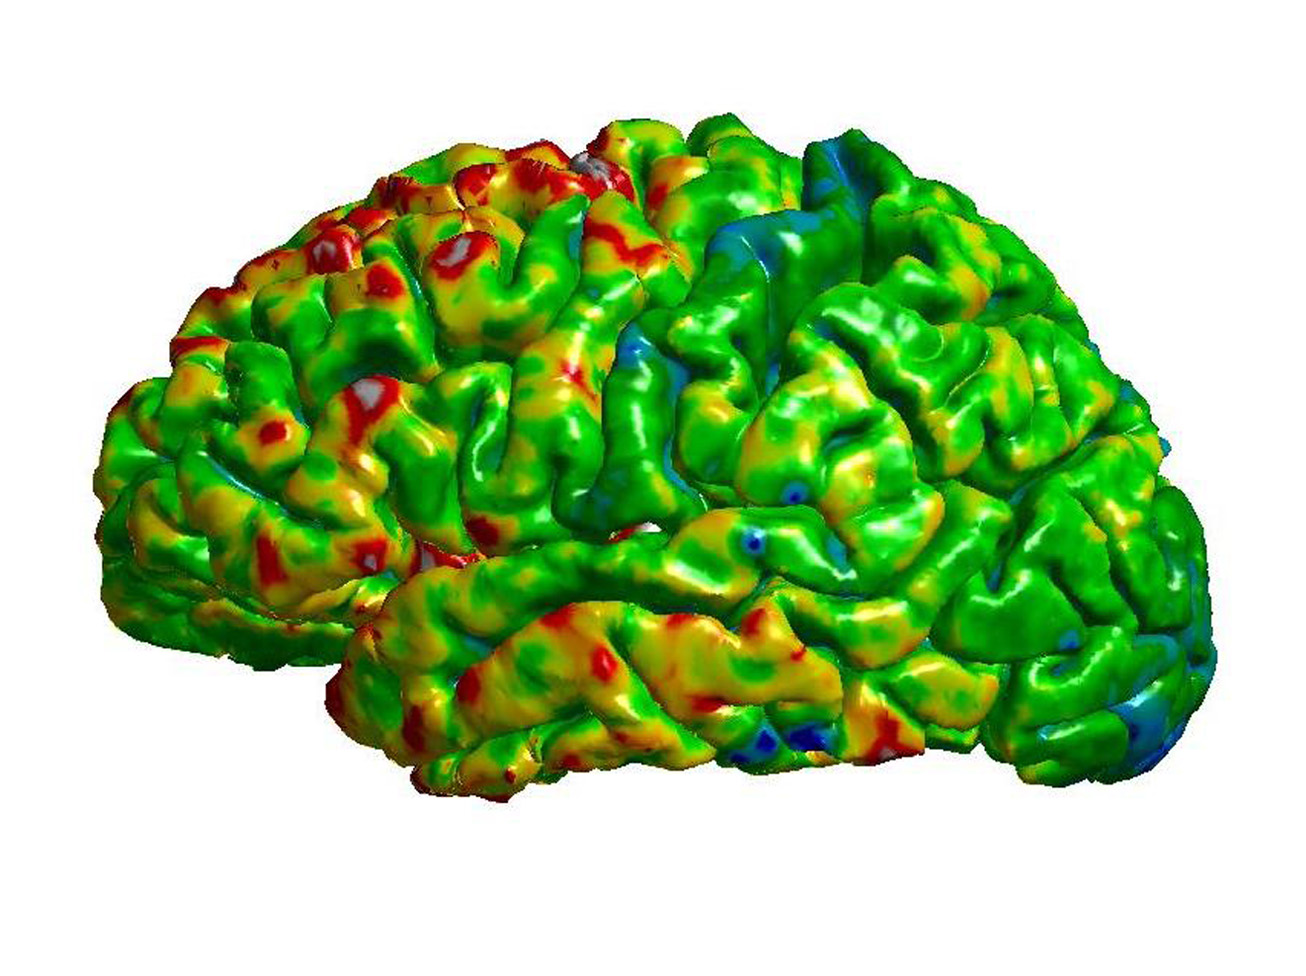

Most research in schizophrenia has been traditionally based on “wide” perspectives and there is an urgent need of circuit-based approaches, which focus on well-identified cerebral regions, their connectivity and their physiology. The thalamus is a very good candidate to perform this directed research, because schizophrenia is characterized by disturbances in both perceptual processing (e.g., hallucinations) and cognitive functions (e.g. impaired working memory), which likely reflect alterations in its structure and function and its connectivity with other cerebral regions, particularly with the neocortex. In fact, there is solid evidence from neuroimaging and postmortem data of alterations in the thalamus of patients with schizophrenia, but there are not multidisciplinary studies focused only on this region and integrating genetic, structural and functional data from clinical and preclinical sources. The general objective of this project is to study how adverse experiences during early life (childhood and adolescence) influence the thalamus, its circuits, the genes involved in their construction and their physiology, and whether these alterations can be predisposing factors for schizophrenia.

The project tackles its main objective using a multidisciplinary and translational approach. We will use animal models of adverse experiences using transgenic mice, combining molecular, structural and connectivity analyses with superresolution microscopy, behavioral tests and transcriptomics. The project also includes analyses of the thalamus of patients using postmortem tissue. Clinical studies will be also performed in living patients using psychological evaluations, expression analysis in blood and in olfactory neurons of genes relevant to thalamic function/plasticity and DNA methylation analysis of candidate genes. We also plan to generate IPSC cells from patients and, through a collaboration, generate thalamic organoids to study gene expression and connectivity. We will also analyze neuroimaging data in structural and functional MRI from patients to determine changes in different thalamic nuclei, as well as in their projecting regions in the cerebral cortex. Finally, we will perform correlation analyses of all neuroimaging, gene expression, epigenetic and organoid data. The project will be performed both in its basic and its clinical parts on males and females.